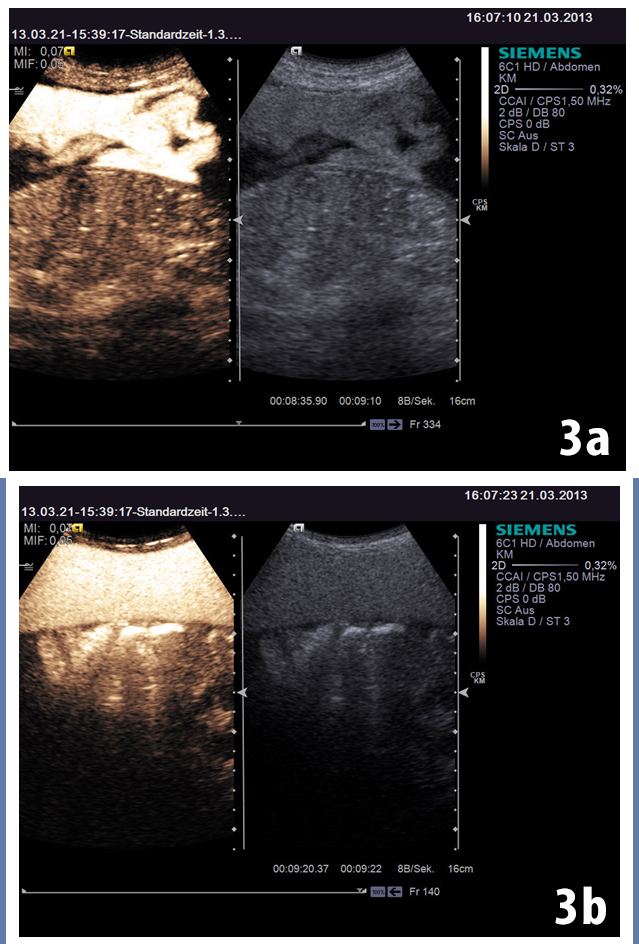

After the intraperitoneally administration of SonoVue® the distribution of the contrast agent was evaluated. The entire pseudocystic lesion was rapidly and homogenously enhanced (Fig 3).

Figure 3: After administered SonoVue intraperitoneally, we evaluated the extension of contrast agents. The whole cystic lesion was rapidly and heterogenous (a) and later homogenously enhancing (b).